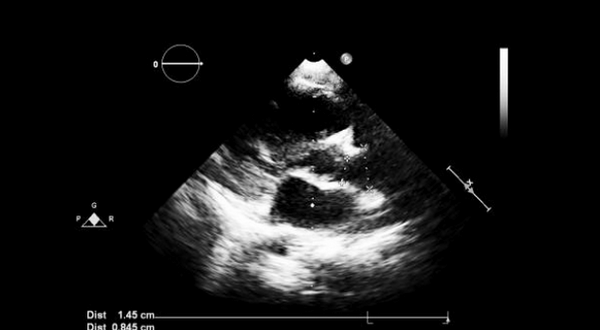

Аортальная недостаточность (АН) — это рефлюкс крови из аорты в ЛЖ во время диастолы. Все методы эхокардиографии полезны в диагностике и оценке аортальной недостаточности. Особенно полезны доплеровские и цветной допплеровский режим. М-режим и двумерная ЭхоКГ не могут напрямую диагностировать АН, но могут указывать на основные причины (например, расширенный корень аорты, двустворчатый аортальный клапан) и помогать в оценке эффектов АН (например, дилатация ЛЖ).

2-D эхокардиография может показать

- Расширение ЛЖ, которая коррелирует с тяжестью АН

- Аномальные створки (двустворчатые, ревматическое поражение)

- Вегетации

- Расширенный корень аорты

- Проксимальное расслоение аорты

- Аномальное вдавливание передней створки МК

- Аномальное движение межжелудочковой перегородки.